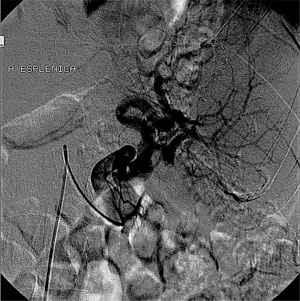

R.F.C, sexo masculino, 68 anos, procedente de Maceió – AL, é portador de hepatite C (genótipo 3a) e de esquistossomose mansônica hepatoesplênica com quadro de hiperesplenismo. Ultrassonografia com doppler de abdome total evidenciou hepatomegalia com sinais de doença parenquimatosa, esplenomegalia e veia esplênica de calibre aumentado. À endoscopia digestiva alta, foi demonstrada gastropatia da hipertensão portal severa, sem erosões antrais, e no hemograma, plaquetopenia (44.600 plaquetas/mm3). O paciente foi submetido à embolização da artéria esplênica (duas sessões) para controle do hiperesplenismo. Com a embolização, 60% do baço foi desvascularizado (Figura 1), havendo aumento do número de plaquetas para 98.200/mm3, e 34 meses após, para 103.000 plaquetas/mm3, possibilitando o tratamento da hepatite.